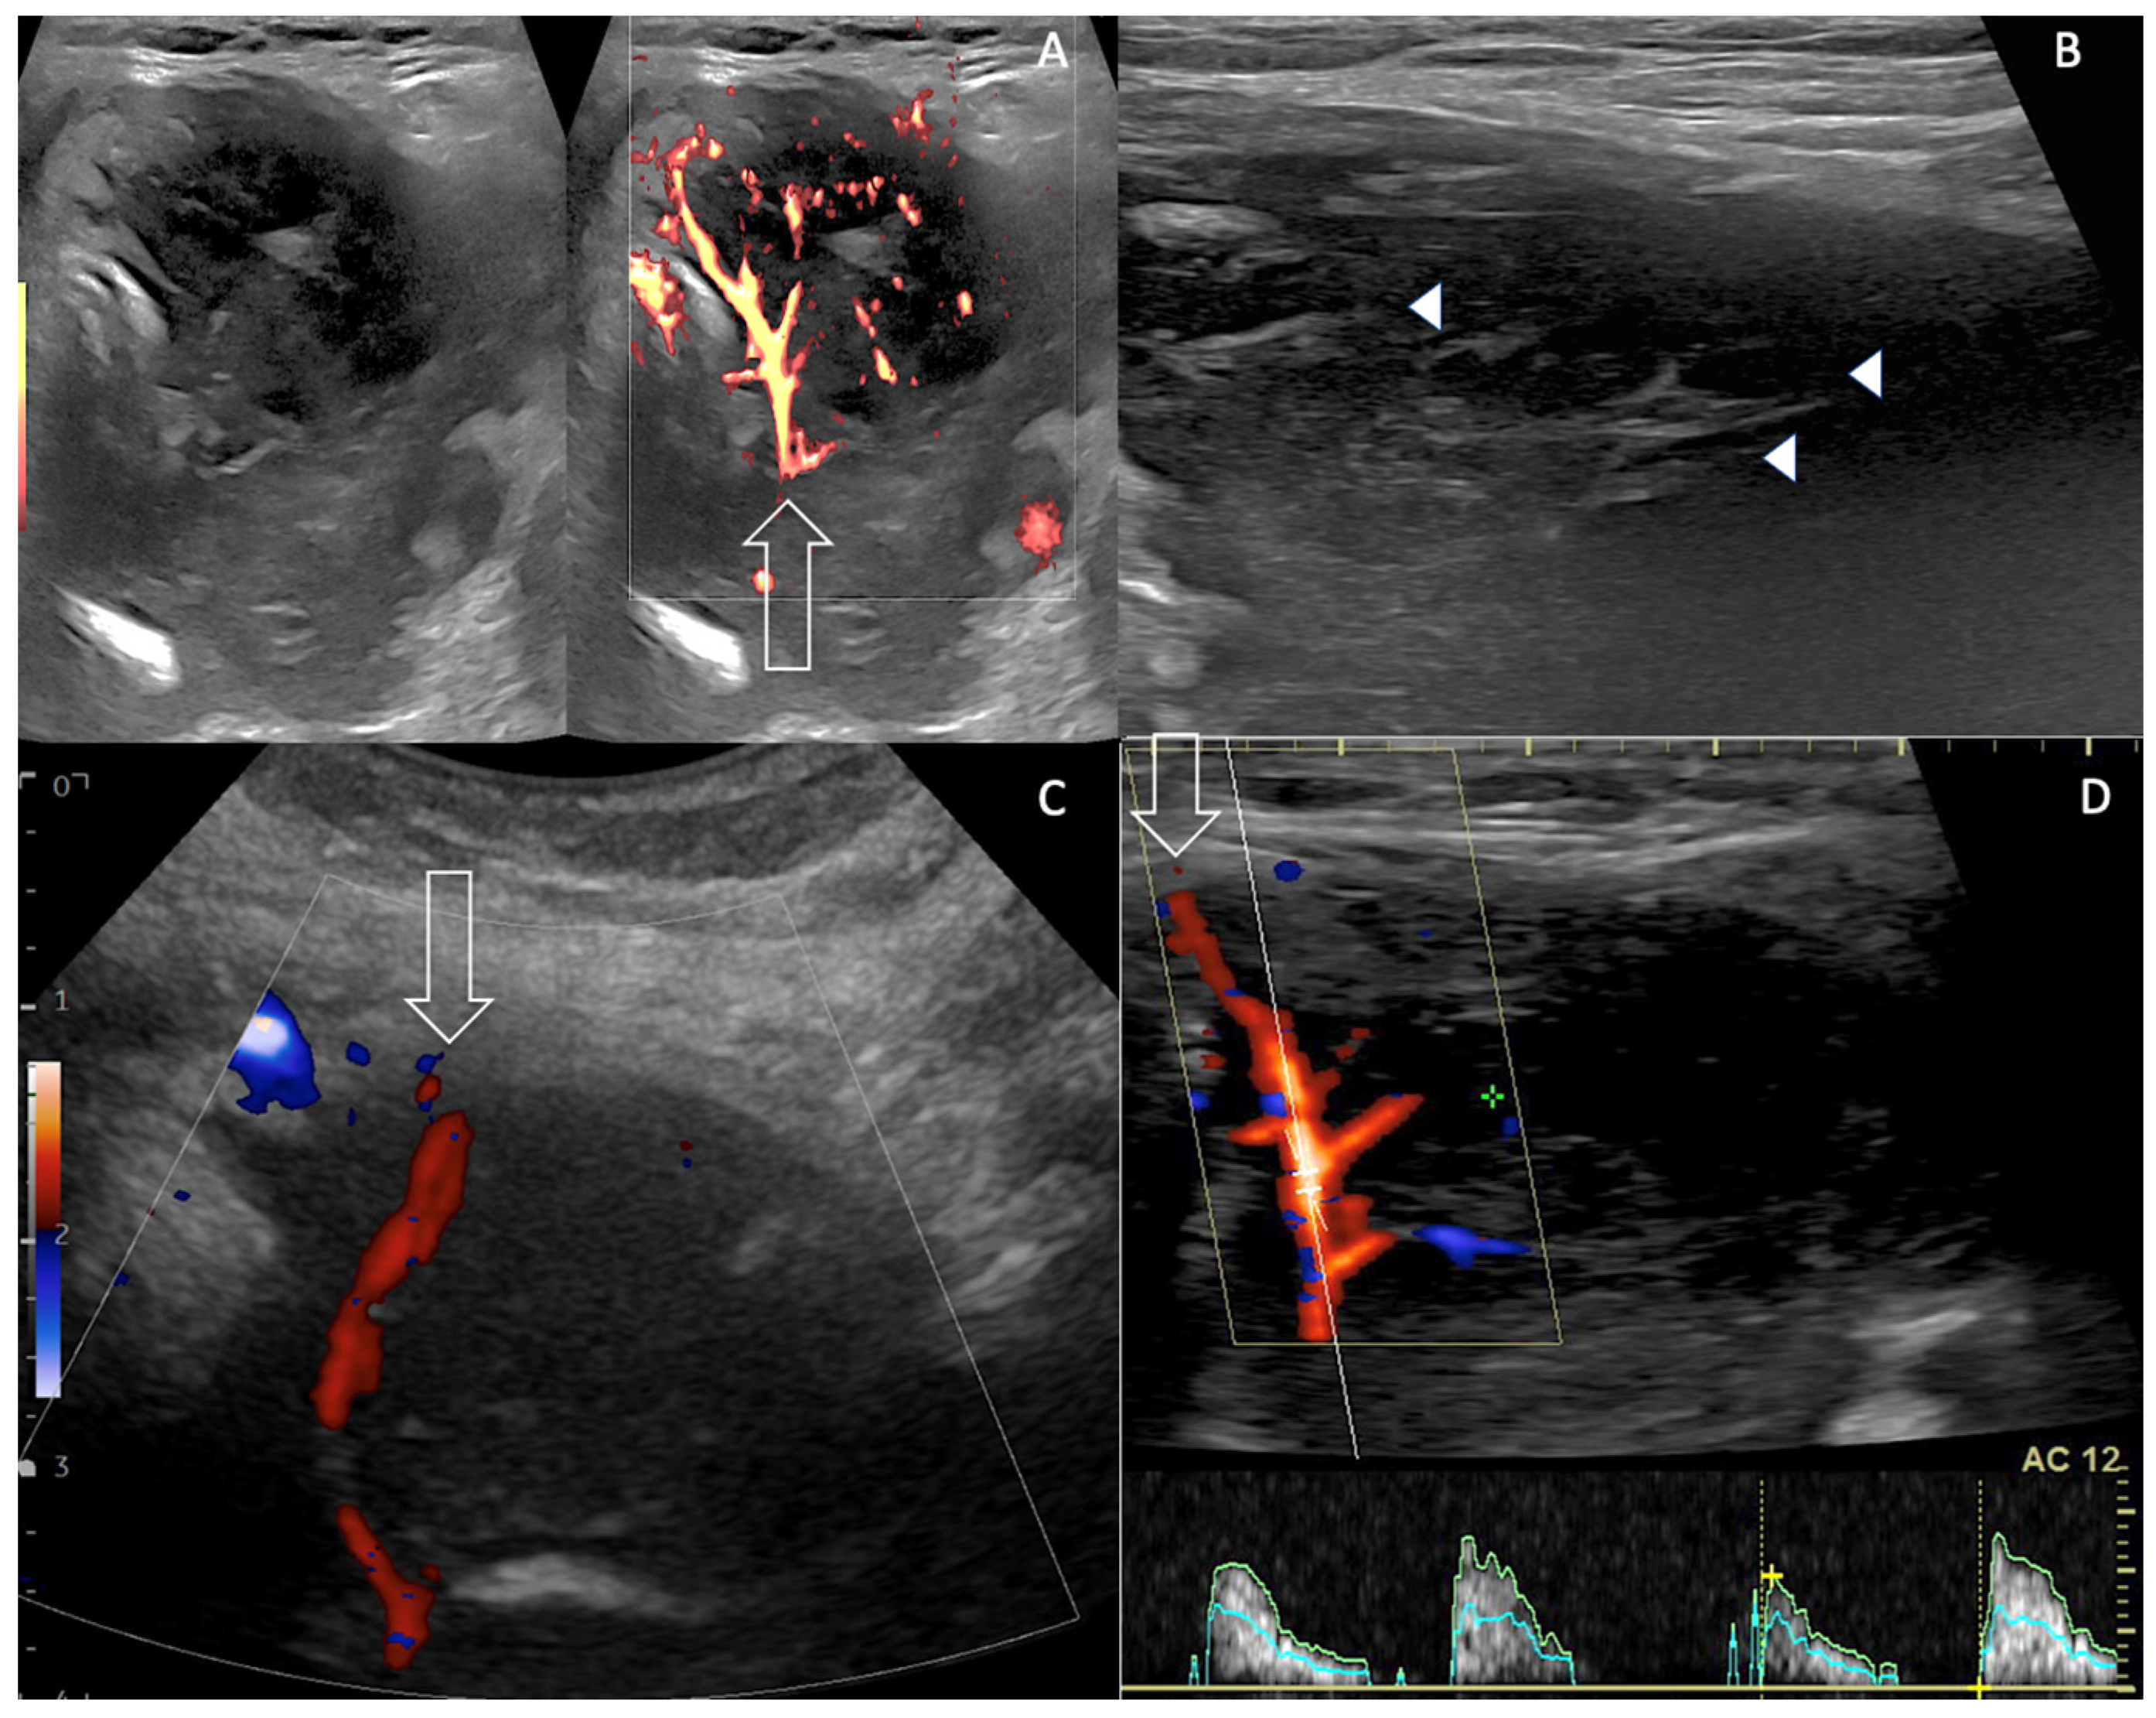

| Imaging Features US Doppler EuTIRADS score IJV invasion Computed Tomography | Reticular pattern More homogeneous than thyroid carcinoma No necrosis/calcification Sword sign Eu-TIRADS 5 Rare No cystic necrosis No gross calcification Homogeneous Nodes +/0 Mild vasculature Unclear boundaries + Vessel invasion not usual Tracheal compression + | No reticular pattern Heterogeneous Necrosis /calcification Sword sign Eu-TIRADS 5 Not rare Cystic necrosis Gross calcifications Heterogeneous Nodes ++/− Few vessels Unclear boundaries ++ Vessel invasion (33%) Tracheal compression ++ | No reticular pattern Inhomogeneous Depends on pre-existing thyroid No Sword sign Eu-TIRADS 5 > Eu-TIRADS 4 Exceptional No cystic necrosis No gross calcification Nodular Nodes +/− Increased Vasculature (renal) Unclear boundaries 0/+ Vessel invasion very rare (renal) Tracheal compression 0/+ |